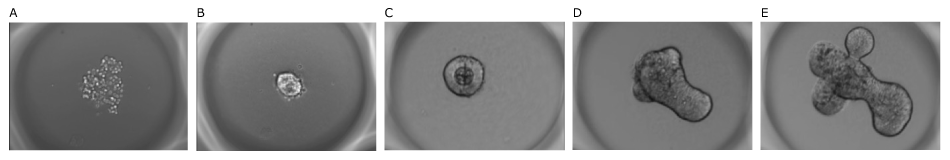

Figure 4.Mouse intestinal organoids grown on Millicell® Microwell plates. A) 1 hour, B) 10 hours, C) 2 hours, D) 3 days, and E) 4 days after seeding.

The organoids were monitored throughout seeding, growth, and imaging; 121 single organoids were developed over time in one well. They were found to be of homogeneous size and were confined to the microwells, facilitating imaging. The mouse intestinal organoids showed typical budding morphology after differentiation and the differentiated intestinal cells expressed specific intestinal markers.

Area of the organoids was quantified through imaging over time in Millicell® Microwell 96-well plates. The organoids were confined to a specific microcavity and were homogeneously sized in the first days 1-3 of growth before broadening as the organoids began budding.